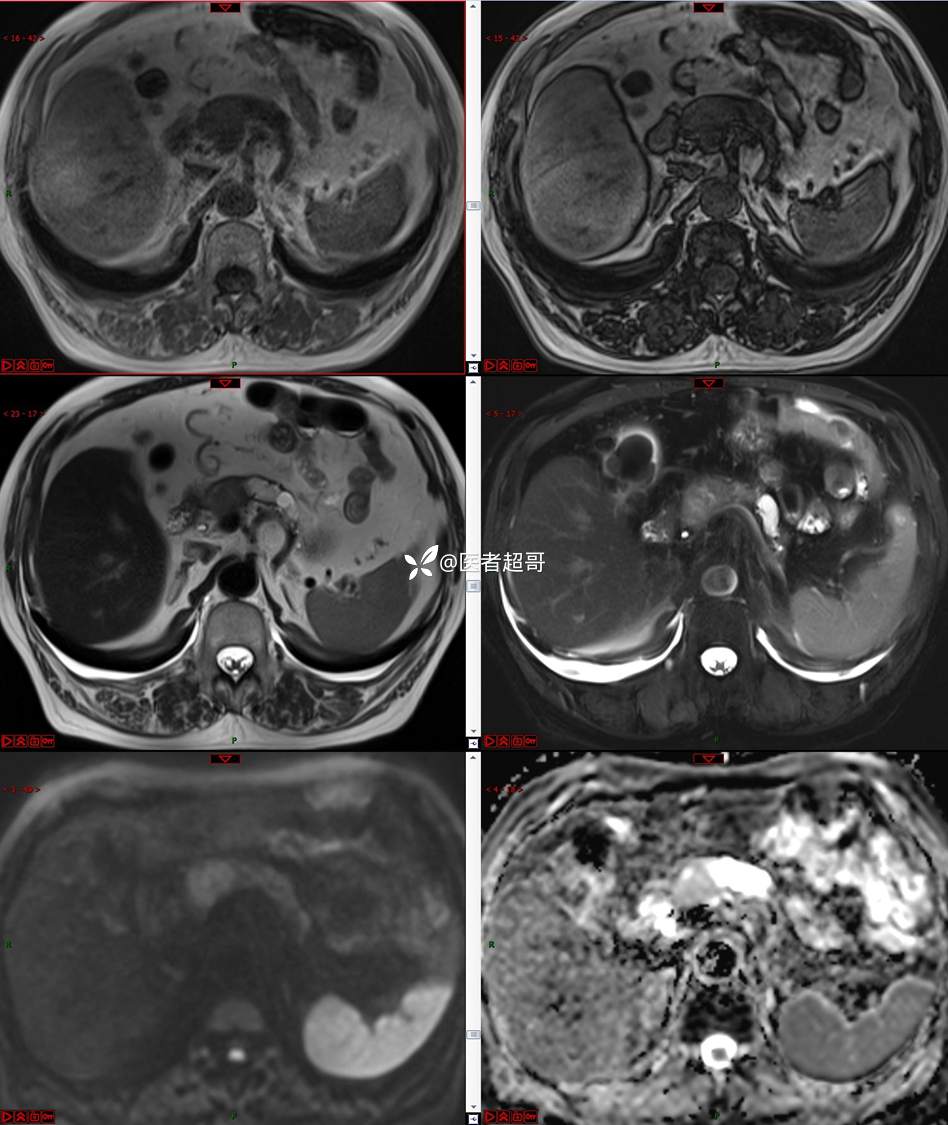

【影诊笔记677】查体发现胰腺占位性病变1周,细节决定成败,请诊断分析!

主 诉:查体发现胰腺占位性病变1周。

现病史:患者1周前在当地查体时发现胰腺占位性病变,无恶心、呕吐,无腹痛,无寒战、高热,无咳嗽、咳痰等异常不适,来我院门诊查上腹部CT平扫+强化:胰腺尾部异常密度灶。今为求进一步治疗,门诊以“胰腺占位性病变”收入院。患者自发病以来,一般情况可,神志清,精神可,普通饮食,二便正常,体重及体力无明显改变。

既往史:既往糖尿病病史2年,口服二甲双胍早晚各一片和格列吡嗪早晚各一片,否认高血压、心脑血管病等疾病史,否认肝炎、结核或其他传染病史及密切接触史,预防接种史不详,否认药物及食物过敏史,否认外伤史,12年前肾癌切除术手术史,否认输血史,其它无特殊。